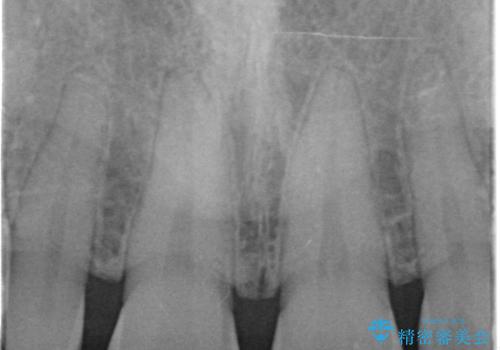

- 前歯の隙間を埋めたいとのことで来院された患者様です。

矯正治療とかぶせ物での治療どちらともご提案したところ、かぶせ物での治療をご希望されたためクラウンでの審美性回復を試みることとなりました。

今回のように、元の歯が小さすぎる場合は矯正治療での審美性回復が難しいことがあります。

形のイメージを反映させた仮歯を調整し、技工士さんと連携して製作したため口元に調和した非常に審美的なクラウンを装着することができました。